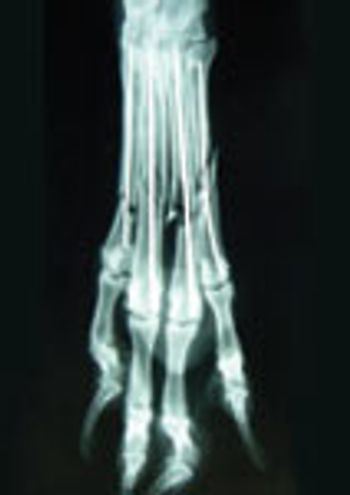

Metacarpal and metatarsal bone fractures are common injuries seen in the dog, typically resulting from automobile trauma, being stepped upon or having the paw trapped under a rigid object.